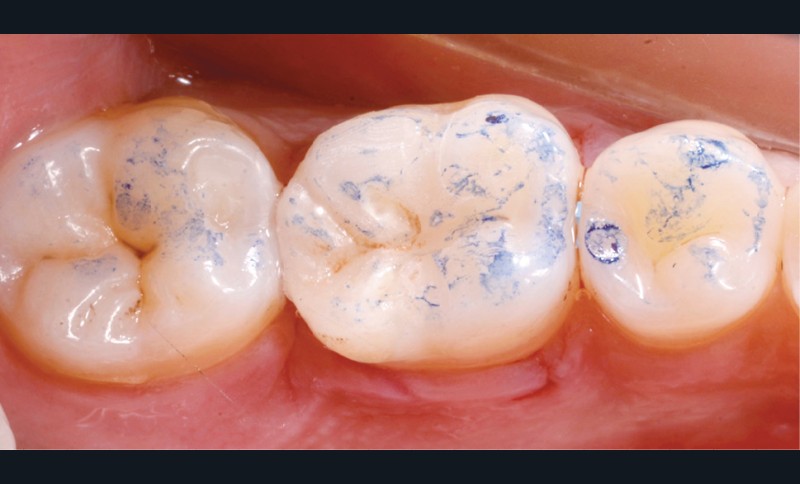

Lors de la préparation d’une cavité pour inlay/onlay, il est fréquent d’être confronté, en fin de nettoyage, à la présence d’une ou plusieurs parois résiduelles dont la résistance mécanique paraît douteuse du fait de leur localisation ou de leur épaisseur. Les parois épaisses (+ de 2 mm) peuvent généralement être conservées (cas clinique 1) et les parois fines (- de 1 mm) doivent généralement être recouvertes. Un inlay (en composite ou en céramique) est alors réalisé. Il doit avoir lui même, au final, une épaisseur globale minimale de 2 mm pour assurer sa résistance mécanique intrinsèque à la mastication. Si un recouvrement cuspidien est indiqué, la réduction occlusale doit donc se faire sur 2 mm de hauteur au minimum [1, 2].

Mais qu’en est-il des parois résiduelles d’épaisseur intermédiaire (entre 1 et 2 mm) (cas clinique 2) ?

S’il est impossible de connaître avec certitude le risque de fracture d’une cuspide, l’objectif de cet article est de donner des éléments objectifs de prise de décision de la conservation ou du recouvrement des parois d’épaisseur moyenne à la fin du nettoyage cavitaire selon la dent, l’occlusion, la forme et le volume de la cavité, la présence ou non de dentine, la vitalité ainsi que l’incidence esthétique.